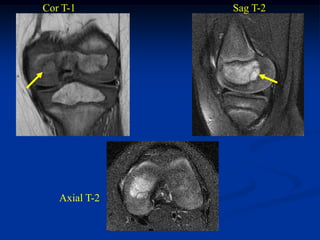

Case #450.1                              Rosai-Dorfman’s disease

52 year old female with knee pain for 1 year

Sag T-1         T-2

Gad

Axial T-1   T-2

Cor T-1         T-2